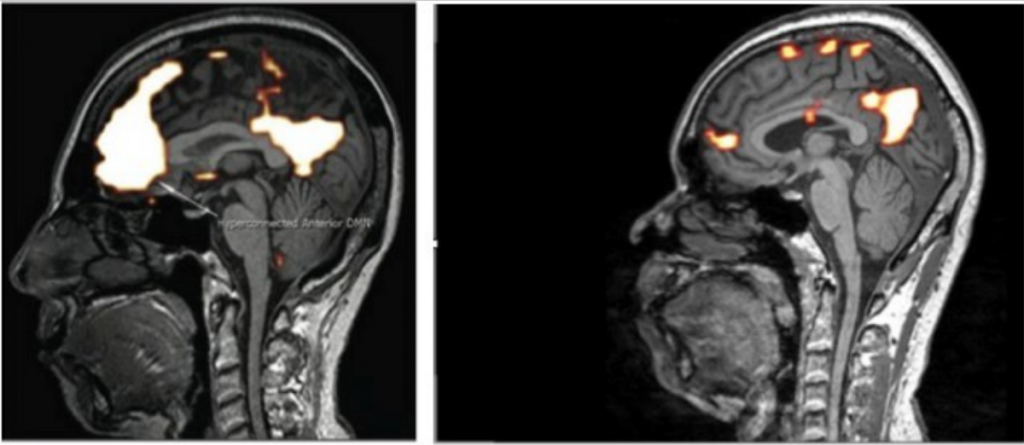

Please click on the above image from our ground breaking study showing the effects of wireless radiation on the brain of “an EHS/electrosensitive (civilian term) or microwave radiation poisoned (military term) individual.